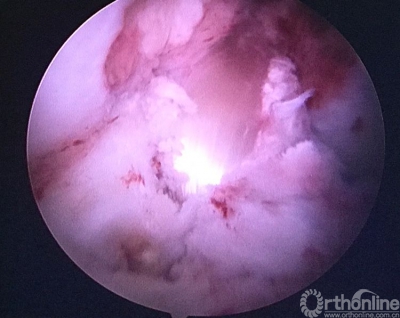

关节镜检查见重建的韧带已经消失。

原来重建的ACL胫骨隧道内口偏前(等离子刀头所指处)。